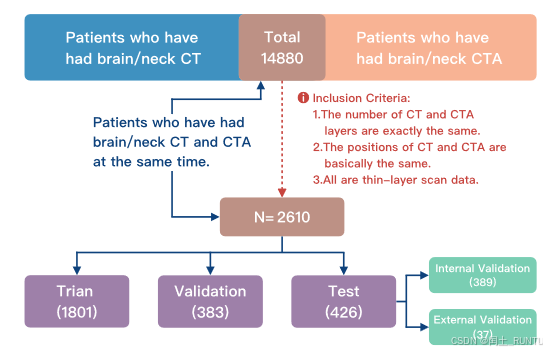

收集了14880例数据,根据纳入标准只纳入了2610例,数据构成:

- 训练集:1801

- 验证集:383

- 测试集:426(进一步分为内部验证389例和外部验证37例)

PS:CT和CTA数据需要精确对齐,并重采样到了0.537mm×0.537mm×0.625mm;文中还提到为保证模型的泛化性,数据集还涉及了多种脑血管疾病,例如颅内动脉瘤、脑动脉粥样硬化、动脉夹层等。但是在诊断性评估中只涉及了动脉瘤和动脉夹层两类疾病的诊断性能。